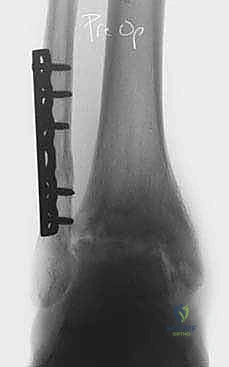

الخطوة الثانية: تركيب الإطار الخارجي (Ilizarov Frame)

هذه هي المرحلة الهندسية الدقيقة. يتم تركيب حلقتين معدنيتين حول عظمة الساق (Tibia) وحلقة ثالثة حول القدم (تثبت في عظمة العقب Talus وعظام مشط القدم).

الخطوة الثالثة: إدخال الأسلاك والمسامير (Wire and Pin Placement)

يتم تمرير أسلاك معدنية رفيعة جداً (Kirschner wires) ومسامير نصفية (Half-pins) عبر العظام لتثبيت الحلقات. يعتمد الأستاذ الدكتور محمد هطيف على معرفته التشريحية العميقة واستخدام جهاز الأشعة المرئي (C-arm) لضمان مرور هذه الأسلاك في "الممرات الآمنة" (Safe corridors) بعيداً عن الشرايين والأعصاب الحيوية.

أثناء العملية، يقوم الدكتور هطيف بإبعاد حلقة الساق عن حلقة القدم تدريجياً وببطء باستخدام قضبان ملولبة، حتى يصل إلى مسافة تشتيت تبلغ حوالي 5 إلى 6 ملليمترات. يتم التأكد من هذه المسافة عبر الأشعة السينية داخل غرفة العمليات.